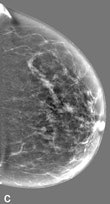

| Example of a subtle finding in a right-sided mediolateral oblique view, which was only reported by radiologists when using premium view (PV). A: Digitized prior. B: Tissue equalization (TE) processed image. C: PV processed image with the annotation. D: The resulting image of subtracting TE from PV. E: Thresholded version of D. White areas indicate that pixels in the PV image have relatively higher intensity than the related pixels in the TE image, whereas black areas indicate the opposite. In PV images, low-frequency trends are suppressed (no noticeable signal decrease in the breast edge in PV compared with TE), whereas higher-frequency structures are emphasized (e.g., glandular structures). All images courtesy of Wouter Veldkamp, PhD, Leiden University Medical Center. |

The local contrast optimization, premium view, has been designed to improve the quality of the information presented to the radiologist for diagnosis and also the reading speed by optimizing the local contrast in breast structures. In premium view, low-frequency structures are obtained from the original image by low-pass filtering. High-frequency structures are obtained by subtracting the low-pass filtered image from the original image. The low- and high-frequency images are both processed and weighted individually, then added together. The resulting image exhibits reduced contrast between different tissue types but enhanced contrast of small-scale anatomical architecture.

Another example of a finding in a left-sided craniocaudal view that was reported clearly more often by radiologists when using premium view (PV). A: Tissue equalization (TE) processed image. B: PV processed image with the annotation. C: Similar to image above, the resulting image of subtracting TE from PV. D: The thresholded version of C.For all six radiologists, perceived case suspiciousness -- defined as the highest probability of malignancy of all radiologist findings -- was higher using premium view optimization.